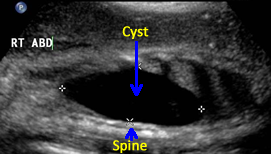

Above. Case 3. 28 3/7 weeks gestation. Transverse view of a cyst in the right upper quadrant.

Above. Case 3. 28 3/7 weeks gestation. Longitudinal view of a cyst in the right upper quadrant. Note the close proximity of the cyst to the fetal spine. On MRI, the kidney is displaced inferiorly and given the potential retroperitoneal location, a duplication cyst of the gastrointestinal tract is a possibility.